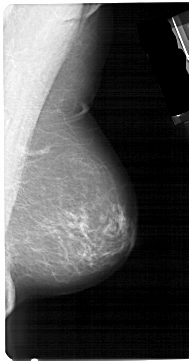

A_1536_1.LEFT_CC

LEFT_CC LINES 4966 PIXELS_PER_LINE 2581 BITS_PER_PIXEL 12 RESOLUTION 43.5 OVERLAY

FILE: A_1536_1.LEFT_CC.OVERLAY

TOTAL_ABNORMALITIES 1

ABNORMALITY 1

LESION_TYPE MASS SHAPE OVAL MARGINS ILL_DEFINED

ASSESSMENT 4

SUBTLETY 3

PATHOLOGY MALIGNANT

TOTAL_OUTLINES 1

BOUNDARY